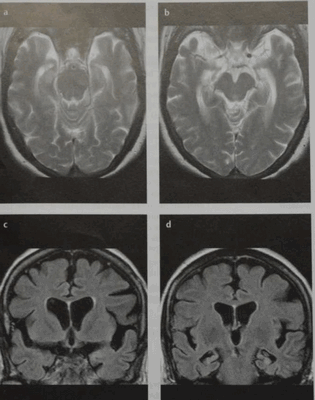

Атрофия головного мозга при болезни Альцгеймера на снимках МРТ: а, b - Т2 ВИ в аксиальной проекции, с, d - режим FLAIR в коронарной плоскости. Визуализируются истончение коры теменной и височной долей, особенно в области гиппокампа. Височные рога боковых желудочков расширены